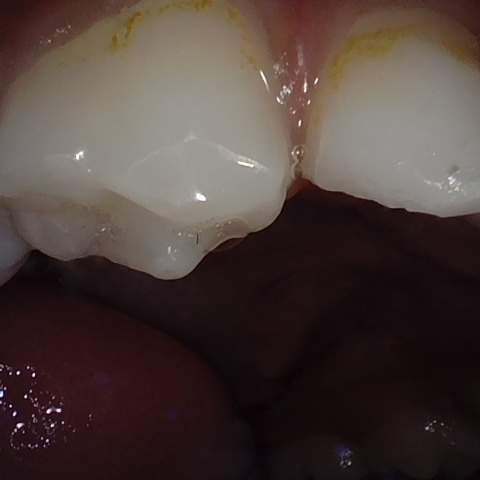

NHD31075

Annotated as "Good"

Original Image Rendering Image